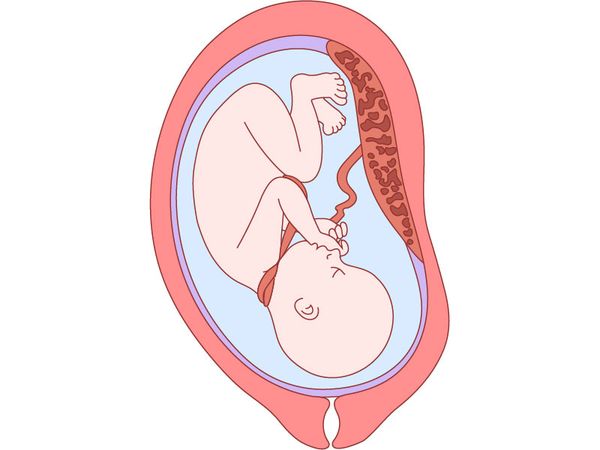

Пуповина (пупочный канатик; канатик жизни) — это шнуровидное образование, которое соединяет пупочную область плода с плацентой (детским местом) и состоит из сосудов, несущих кровь от плода к плаценте и обратно. Пуповина анатомически входит в состав последа (того, что рождается после младенца).

Ребёнок развивается в матке, а именно в околоплодном пузыре, заполненном околоплодными водами. Их количество к концу беременности достигает объёма от 500 мл до 1,5 л. В них двигается плод, а пуповина свободно перемещается вместе с ним. Во время внутриутробного роста естественные движения необходимы малышу для нормального развития, поэтому его положение и положение пуповины в матке меняется [9].

В норме пуповина представляет собой винтообразный, скрученный слева направо канатик, внутри которого расположены три сосуда: одна вена и две артерии. Число витков пупочного канатика зависит от его длины и может разниться от 10 до 25 [8].

Строение пуповины

Сосуды пуповины окружены веществом, которое называют вартоновым студнем. Оно играет важную роль: обеспечивает упругость пупочного канатика, предохраняет пуповину от сдавления, осуществляет обмен веществ между кровью плода и околоплодной жидкостью [4]. Диаметр сосудов пуповины постоянен, меняется только толщина вартонова студня.

Зачаток пуповины формируется на 2-й неделе развития эмбриона (15-17-й день) и растёт в длину вместе с плодом: более интенсивно в период с 20-й до 27-й недели беременности, а затем темпы её роста снижаются [6]. Широко известно точное высказывание Леонардо Да Винчи: «Длина пуповины должна соответствовать длине плода при конкретном сроке беременности» [1].